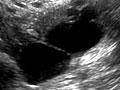

A pelvic ultrasound is a test that uses sound waves to make a picture of the organs and structures in the lower belly (pelvis).

Organs and structures that are solid and uniform (such as the uterus, ovaries, or prostate gland) or that are fluid-filled (such as the bladder) show up clearly on a pelvic ultrasound. Bones may block other organs from being seen. Air-filled organs, such as the intestines, can make the image less clear.

In all of these ultrasounds, the transducer sends the reflected sound waves to a computer, which makes them into a picture that is shown on a video screen. Ultrasound pictures or videos may be saved as a permanent record.